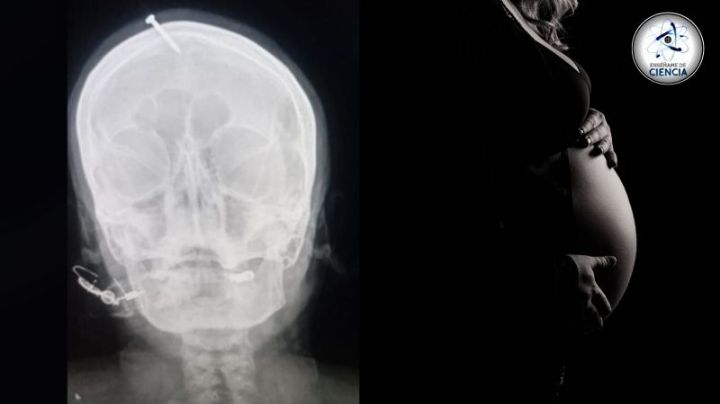

Curandero "martilla" un clavo en la cabeza de una mujer embarazada para darle un varón

15/2/2022 | La mujer, madre de tres hijas, buscaba por fin dar un niño a su pareja, requiriendo el tan ofertado rito del hechicero.